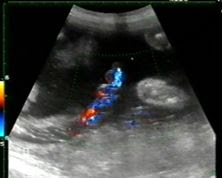

Anno 2008 Numero 161 del 14-03-2008  Parte a Noventa Vicentina (Vicenza) il progetto pilota regionale, per sensibilizzare le donne immigrate alla donazione del cordone ombelicale. L'iniziativa e' promossa da ADoCes Associazioni Donatori Cellule Staminali e dal Coordinamento delle Ostetriche del Veneto che hanno costituito un Gruppo di Lavoro per studiare un percorso di donazione per le mamme straniere. Nel Veneto e' possibile donare presso molte unita' di ostetricia che inviano le raccolte presso le tre banche di crioconservazione istituite dalla Regione Veneto presso le Aziende ospedaliere di Padova, Treviso e Verona. La donazione e' volontaria, anonima e gratuita e non comporta alcun rischio medico per la madre e il neonato e nessun problema etico. L'Unita' Operativa di Ostetricia e Ginecologia di Noventa Vicentina, diretta dal Vincenzo Tinelli, vuole ora sensibilizzare le mamme immigrate sempre piu' presenti nelle corsie dei reparti maternita'. L'iniziativa e' sostenuta da una campagna informativa con poster nelle sette lingue piu' rappresentative e da una brochure in lingua italiana. Il Gruppo di Lavoro ha inoltre studiato un Manuale operativo 'Percorsi multilingue per la donazione del sangue cordonale' utilizzato dalle ostetriche durante il colloquio con la donna per agevolare la comprensione per una donazione consapevole, responsabile e sicura.